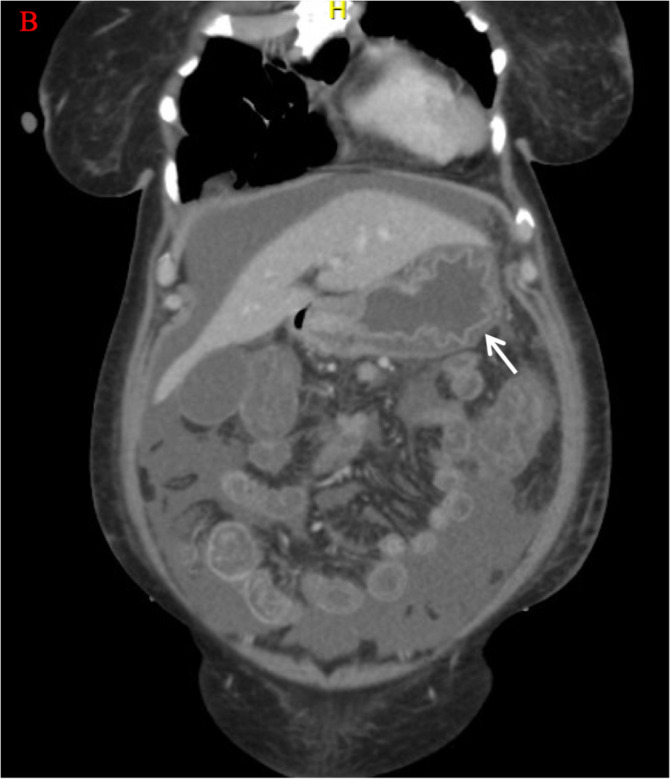

Lupus enteritis is a rare gastrointestinal complication of systemic lupus erythematosus (SLE) associated with significant morbidity and mortality. Rituximab, a monoclonal antibody targeting CD20-positive B cells, has shown promise in refractory SLE cases. We present a case of a 45-year-old female with SLE who developed lupus enteritis and experienced an unusually rapid and remarkable response to Rituximab. The patient presented with severe abdominal pain and distension. Within two days of Rituximab treatment, the patient's abdominal pain, distension, and associated complications resolved completely. This exceptional response challenges the typical timeline of Rituximab efficacy in SLE and highlights the need for further investigation into the factors influencing treatment response. Understanding the mechanisms underlying such rapid improvement may provide insights into SLE pathogenesis and guide therapeutic strategies for optimal outcomes.

Abstract Image